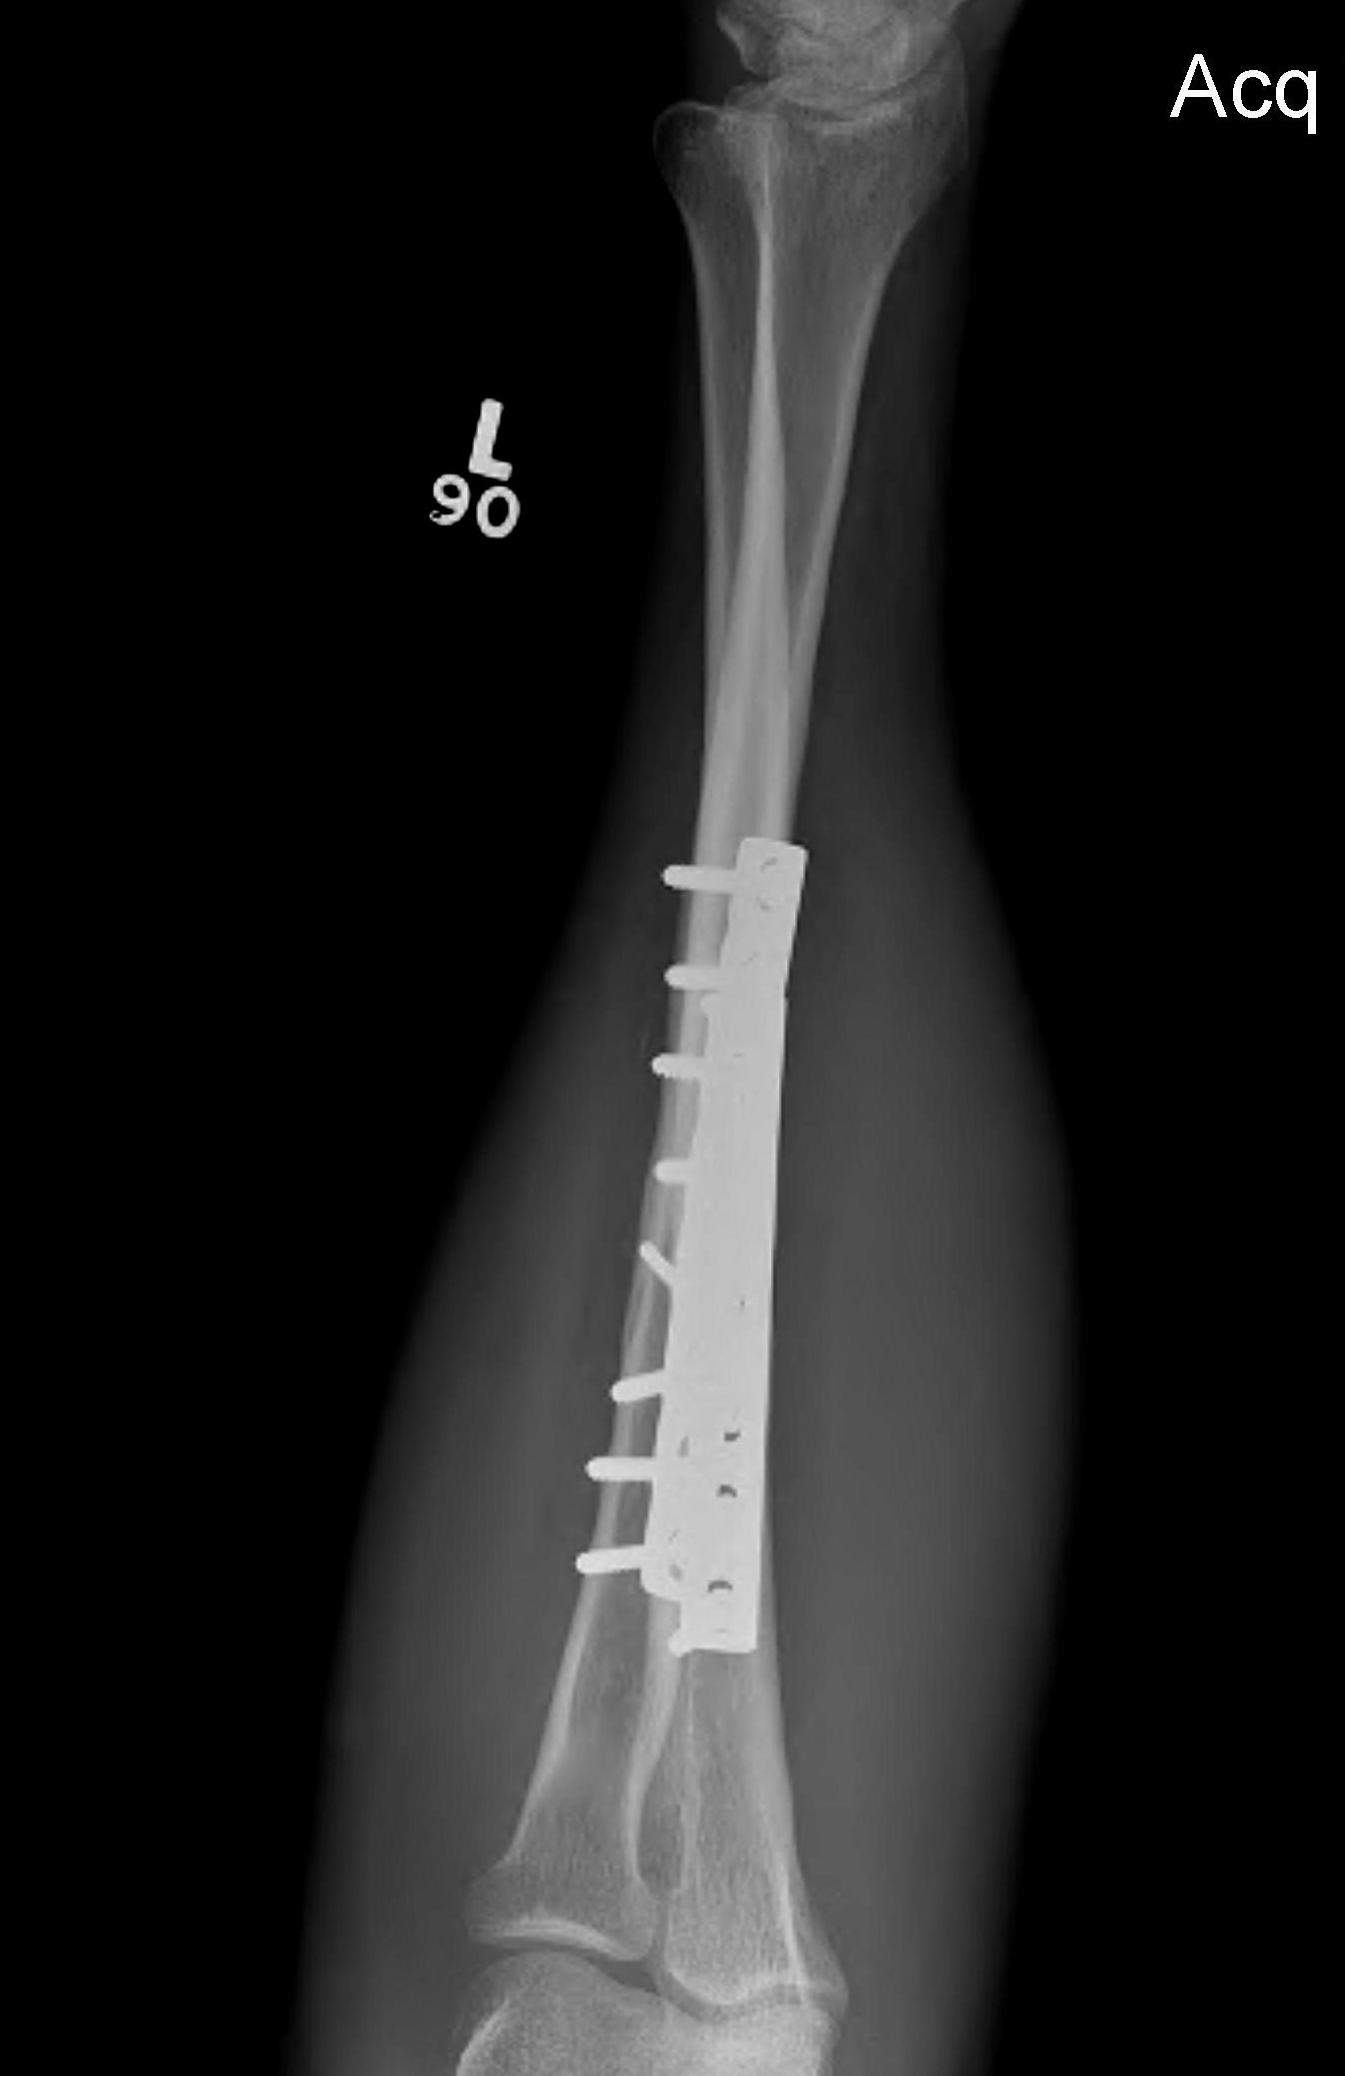

ORIF with plates

ORIF with DCP plates

Fixation with DCP plates